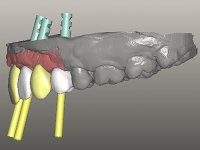

O paciente foi observado conjuntamente e a dúvida que surgiu de imediato foi se seria possível com a regeneração óssea a efectuar poder ser reabilitada naturalmente a zona das papilas interdentárias. Nesse sentido foi feito um enceramento de diagnóstico que contemplaria as duas hipóteses, utilizando ou não a cerâmica gengival. A confecção desse enceramento foi fundamental para expor ao paciente a dificuldade da reabilitação. O wax-up deu origem a um mock-up que foi aprovado pelo paciente e que simultaneamente serviu de guia imagiológica. O caso foi planificado cirurgicamente e realizada uma guia cirúrgica com que foram colocados os implantes. Após 10 semanas foi feita a 1ª impressão para confecção da ponte provisória. Foram criados os primeiros perfis de emergência na gengiva artificial e foi digitalizado o modelo. Por processo de CAD-CAM foi confeccionada uma ponte provisória aparafusada baseada no enceramento de diagnóstico. A ponte trabalhou durante 8 semanas os tecidos moles que foram fielmente copiados numa impressão com técnica de moldeira aberta. Os transferes foram individualizados com resina composta para copiarem fielmente os perfis de emergência criados pela ponte provisória. Confeccionado o modelo de trabalho definitivo, foi realizada uma infra-estrutura em zircónio seguindo a orientação do enceramento de diagnóstico. O assentamento da infra-estrutura foi testado em boca e simultaneamente foi novamente impressionados os tecidos moles com um silicone fluido. Nessa consulta foi feito o levantamento da cor. Os dentes 13 e 23 apresentavam uma saturação anormalmente forte que resolvemos não valorizar, optando por privilegiar a relação com o sector antero-inferior. Foi realizada uma nova gengiva artificial com a impressão que acompanhou a impressão de arrasto com a infra-estrutura. Após a colocação da cerâmica na infra-estrutura foram coladas as meso-estruturas. O trabalho final foi aparafusado lentamente permitindo a adaptação dos tecidos moles.